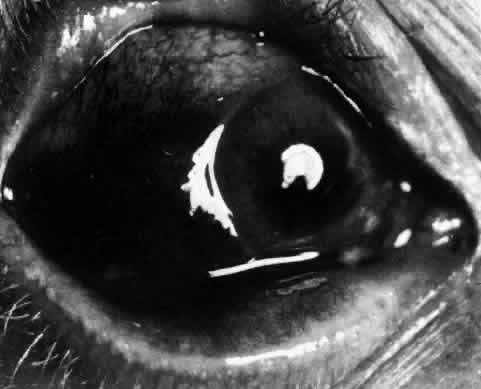

The redness of simple episcleritis may be intense, varying from a fiery-red or a brick-red discoloration to a mild red flush, but it does not have the bluish tinge that is seen in scleritis. The distribution is usually sectorial but can involve the whole anterior segment of the globe. The episcleral vessels are engorged but retain their normal radial position and architecture (Figs. 13 and 14; Color Plate 1A). In simple episcleritis, there is a diffuse edema of the episcleral tissues. These tissues are sometimes infiltrated with gray deposits that appear yellow in red-free light. Surprisingly, the eye is rarely tender to the touch.

Fig. 13. Infiltration of the episclera in which the superficial episcleral vessels show maximal congestion. Conjunctival vessels are slightly congested, as is the deep episcleral plexus, whose irregular criss-cross pattern can be seen deep to the radially arranged superficial episcleral plexus.

Fig. 14. Diffuse inflammation. Superficial vessels are maximally engorged and retain their radial pattern and architecture. (See Figures 27 and 34.) (Watson PG: Connective tissue disorders and the eye. In: Recent Advances in Ophthalmology, Vol 5, pp 214–277. London, Churchill-Livingstone, 1975)